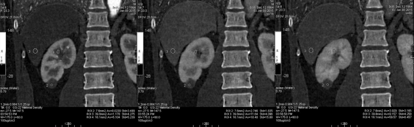

3. 进行能谱分析,碘含量测量,三期病变内部碘含量相似,且接近0的水平,提示病变没有强化。

4. 三期冠状位测量结果显示同样结果;而肝实质、肾脏髓质均有明显强化。